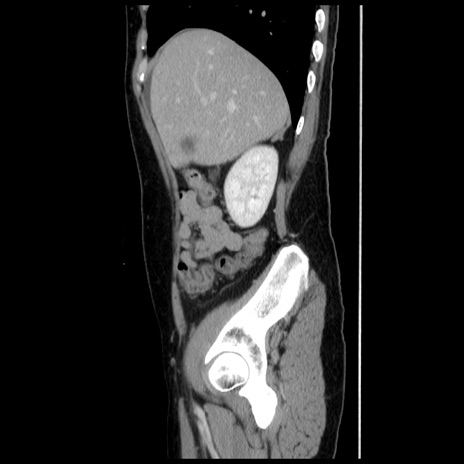

症例10(矢状断像)

【症例】 50歳代女性

【主訴】 腹痛

【現病歴】前日生レバーを食べた。今朝に排便あり。 昼前に突然発症の腹痛を生じ、当院救急外来を受診した。

【既往歴】 子宮筋腫にてで子宮全摘後

【身体所見】 意識清明、腹部:平坦、軟、下腹部やや左を中心に圧痛・反跳痛あり、筋性防御あり

【データ】WBC 7800、CRP 0.07